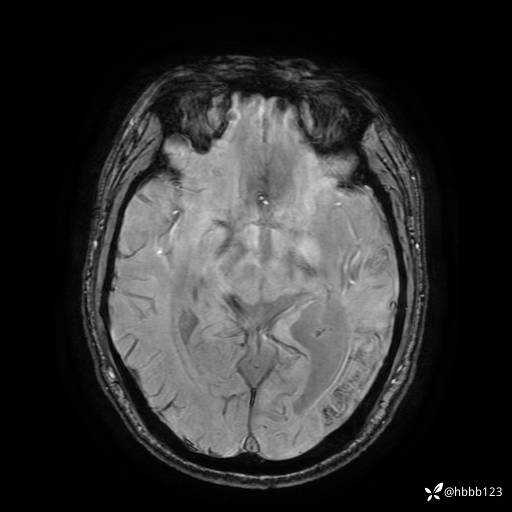

ADC:

3d T1: